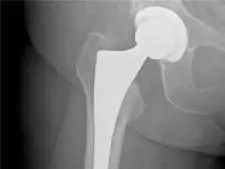

Remplacement total de la hanche à l’aide d’un système robotisé

Ce clip réalisé avec le Dr. Karkare a récemment a été présenté sur une filiale de NBC à Palm Springs, au cours d’un segment video sur le remplacement de la hanche à l’aide d’un système robotisé.

Arthroplastie assitée par robot de la hanche

En chirurgie articulaire assistée par robot, la technologie informatique est utilisée pour aider le chirurgien à mieux contrôler les aspects très précis du processus de remplacement d’une articulation, permettant un positionnement plus précis de l’implant et l’alignement approprié des éléments des articulations artificielles.

À ses pratiques, le Dr. Karkare s’appuie sur le système de pointe assisté par robot de MAKO plastie® pour une meilleure implantation et des résultats reproductibles, fondés sur l’anatomie particulière de chaque patient.

Les chirurgies de la hanche assistées par robot sont réalisées en utilisant une approche chirurgicale par voie antérieure, méthode avec préservation tissulaire qui entraîne moins de traumatisme tissulaire, mais aussi une période de récupération plus rapide et plus confortable.